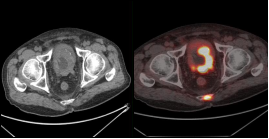

治疗前 治疗后

淋巴瘤治疗前后变化: 弥漫性大B细胞淋巴瘤化疗3程后,腹腔及腹膜后多发肿大淋巴结明显缩小,糖代谢明显减低。

(上两图为:治疗前,下两图为:治疗后)

淋巴瘤治疗前后变化:弥漫性大B细胞淋巴瘤化疗3程后,腹腔机腹膜后多发肿大淋巴结明显缩小,糖代谢明显减低。根据Deauville标准 5PS评分为2分。